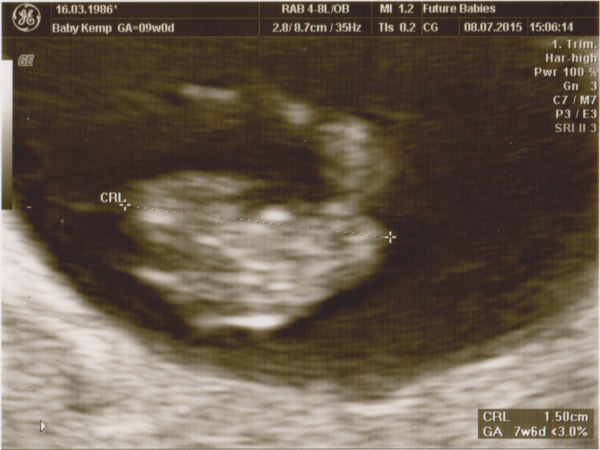

Not as exciting as Montagues' will be cause I'm only 7+3 or so and it's a blob so far... but voila scan pic from yesterday! Congrats Montagues Smile

Elephant, fx for you, it'll be fine!